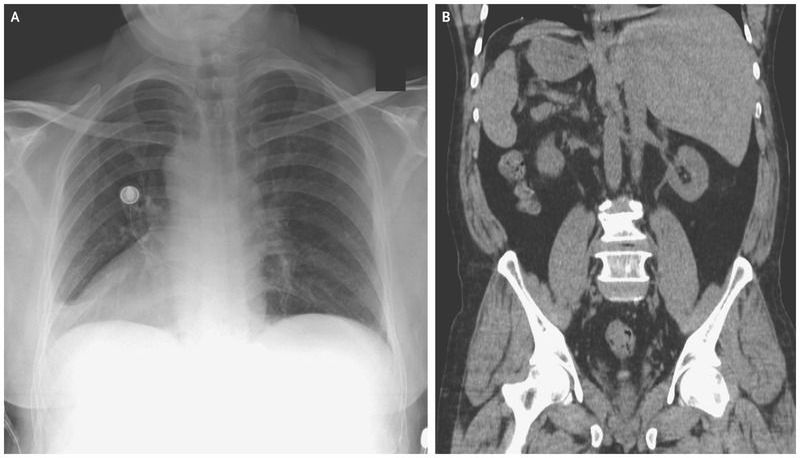

A 66-year-old man presented to the emergency department with a 3-day history of cough, congestion, and pain in his chest and the left side of his abdomen. Several months before presentation, he had immigrated to the United States after living in a refugee camp for 20 years. The results of the physical examination were notable for heart sounds best heard on the right side of the chest and for tenderness in the costochondral joints and the left upper quadrant on palpation. An electrocardiogram showed right axis deviation, reverse precordial R-wave progression, and inverted P waves in leads I, aVL, and aVR Findings on a chest radiograph included dextrocardia (Panel A), and computed tomography of the abdomen revealed mirror-image transposition of the abdominal organs (Panel B), confirming the presence of situs inversus totalis without acute pathologic features. Situs inversus totalis can occur in isolation or in conjunction with primary ciliary dyskinesia. The patient had no history of recurrent respiratory infections suggestive of primary ciliary dyskinesia. Echocardiography revealed no structural abnormalities. A diagnosis of upper respiratory infection was made, and the musculoskeletal chest pain was treated with nonsteroidal antiinflammatory drugs. The infection resolved several days after presentation.